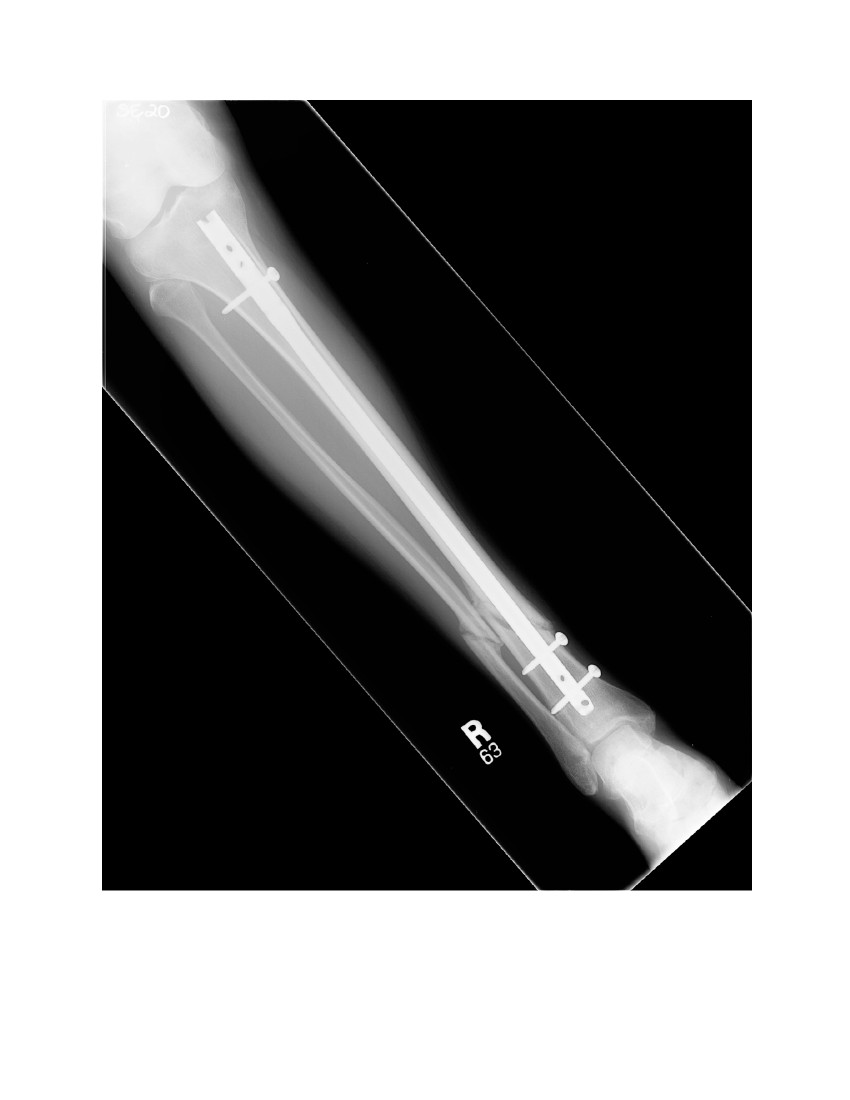

@Phyremedic You may have more screws...but I have bigger ones Tib-Fib after 5 months...

Attached Pictures

Yeah, what happened? You're gonna set off metal detectors with all the metal that it appears they put in there. So sorry this happened to you.

Yeah it's a trimalleolar fracture yesterday I was up and about sort of moving around and I'm not supposed to but I'm strong and I like to get myself back up and going again I'm still in the splint with crutches and I guess I'm supposed to have an operation but really not looking forward to it since I don't really have insurance either I did set up a GoFundMe account so let me know and thanks for all the kind wishes everybody I appreciate it a lot this is definitely a pain that's for sure

is all that metal hardware permanent? bone doesn't grow back together or heal? is it cuz of the type of break? or location of the break? curious why some people get metal installed vs those that don't.